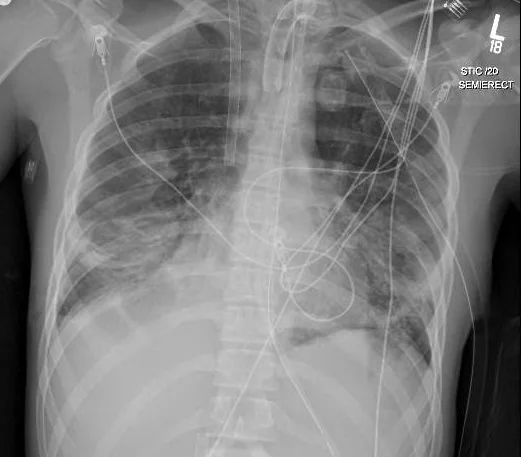

In preparation for cannulation, baseline coagulation studies including an ACT and a TEG with LY30 were checked, and he was then prepped for femoral and IJ cannulation. Once wire access was obtained, he was given a 100U/kg bolus of unfractionated heparin, followed by a 100g/kg bolus of the antifibrinolytic Amicar (epsilon aminocaproic acid), and then the cannulas were inserted and connected to the circuit. Flow was established, the ventilator settings were reduced to “rest” mode to protect his lungs and decrease his CVP, and the circuit sweep gas was used to reduce his pCO2 gradually, with a dramatic drop in his pCO2, likely from both actions. Low level heparin anticoagulation infused into the venous side of the circuit was maintained with lower anti-Xa goals, and an Amicar infusion at 30mg/kg/hr was started after the initial bolus, with periodic TEG-LY30 checks to make sure we were suppressing fibrinolysis sufficiently. On ECMO day 2 Joshua had a repeat head CT (below) and also had a tracheostomy performed at bedside. With his continued improvement in his intracranial pressures, the pentobarbital was stopped, and the ventricular drain was removed. After 13 days of VV support he had a final CXR and a repeat head CT (below) and he was successfully weaned and decannulated from ECMO. He subsequently woke up and was weaned to trach collar 1 week post decannulation. He later left the ICU, and after 2 more weeks he was transferred to rehab, and after three weeks there he was finally able to go home, with continued out-patient therapy and follow-up for his traumatic brain injury.